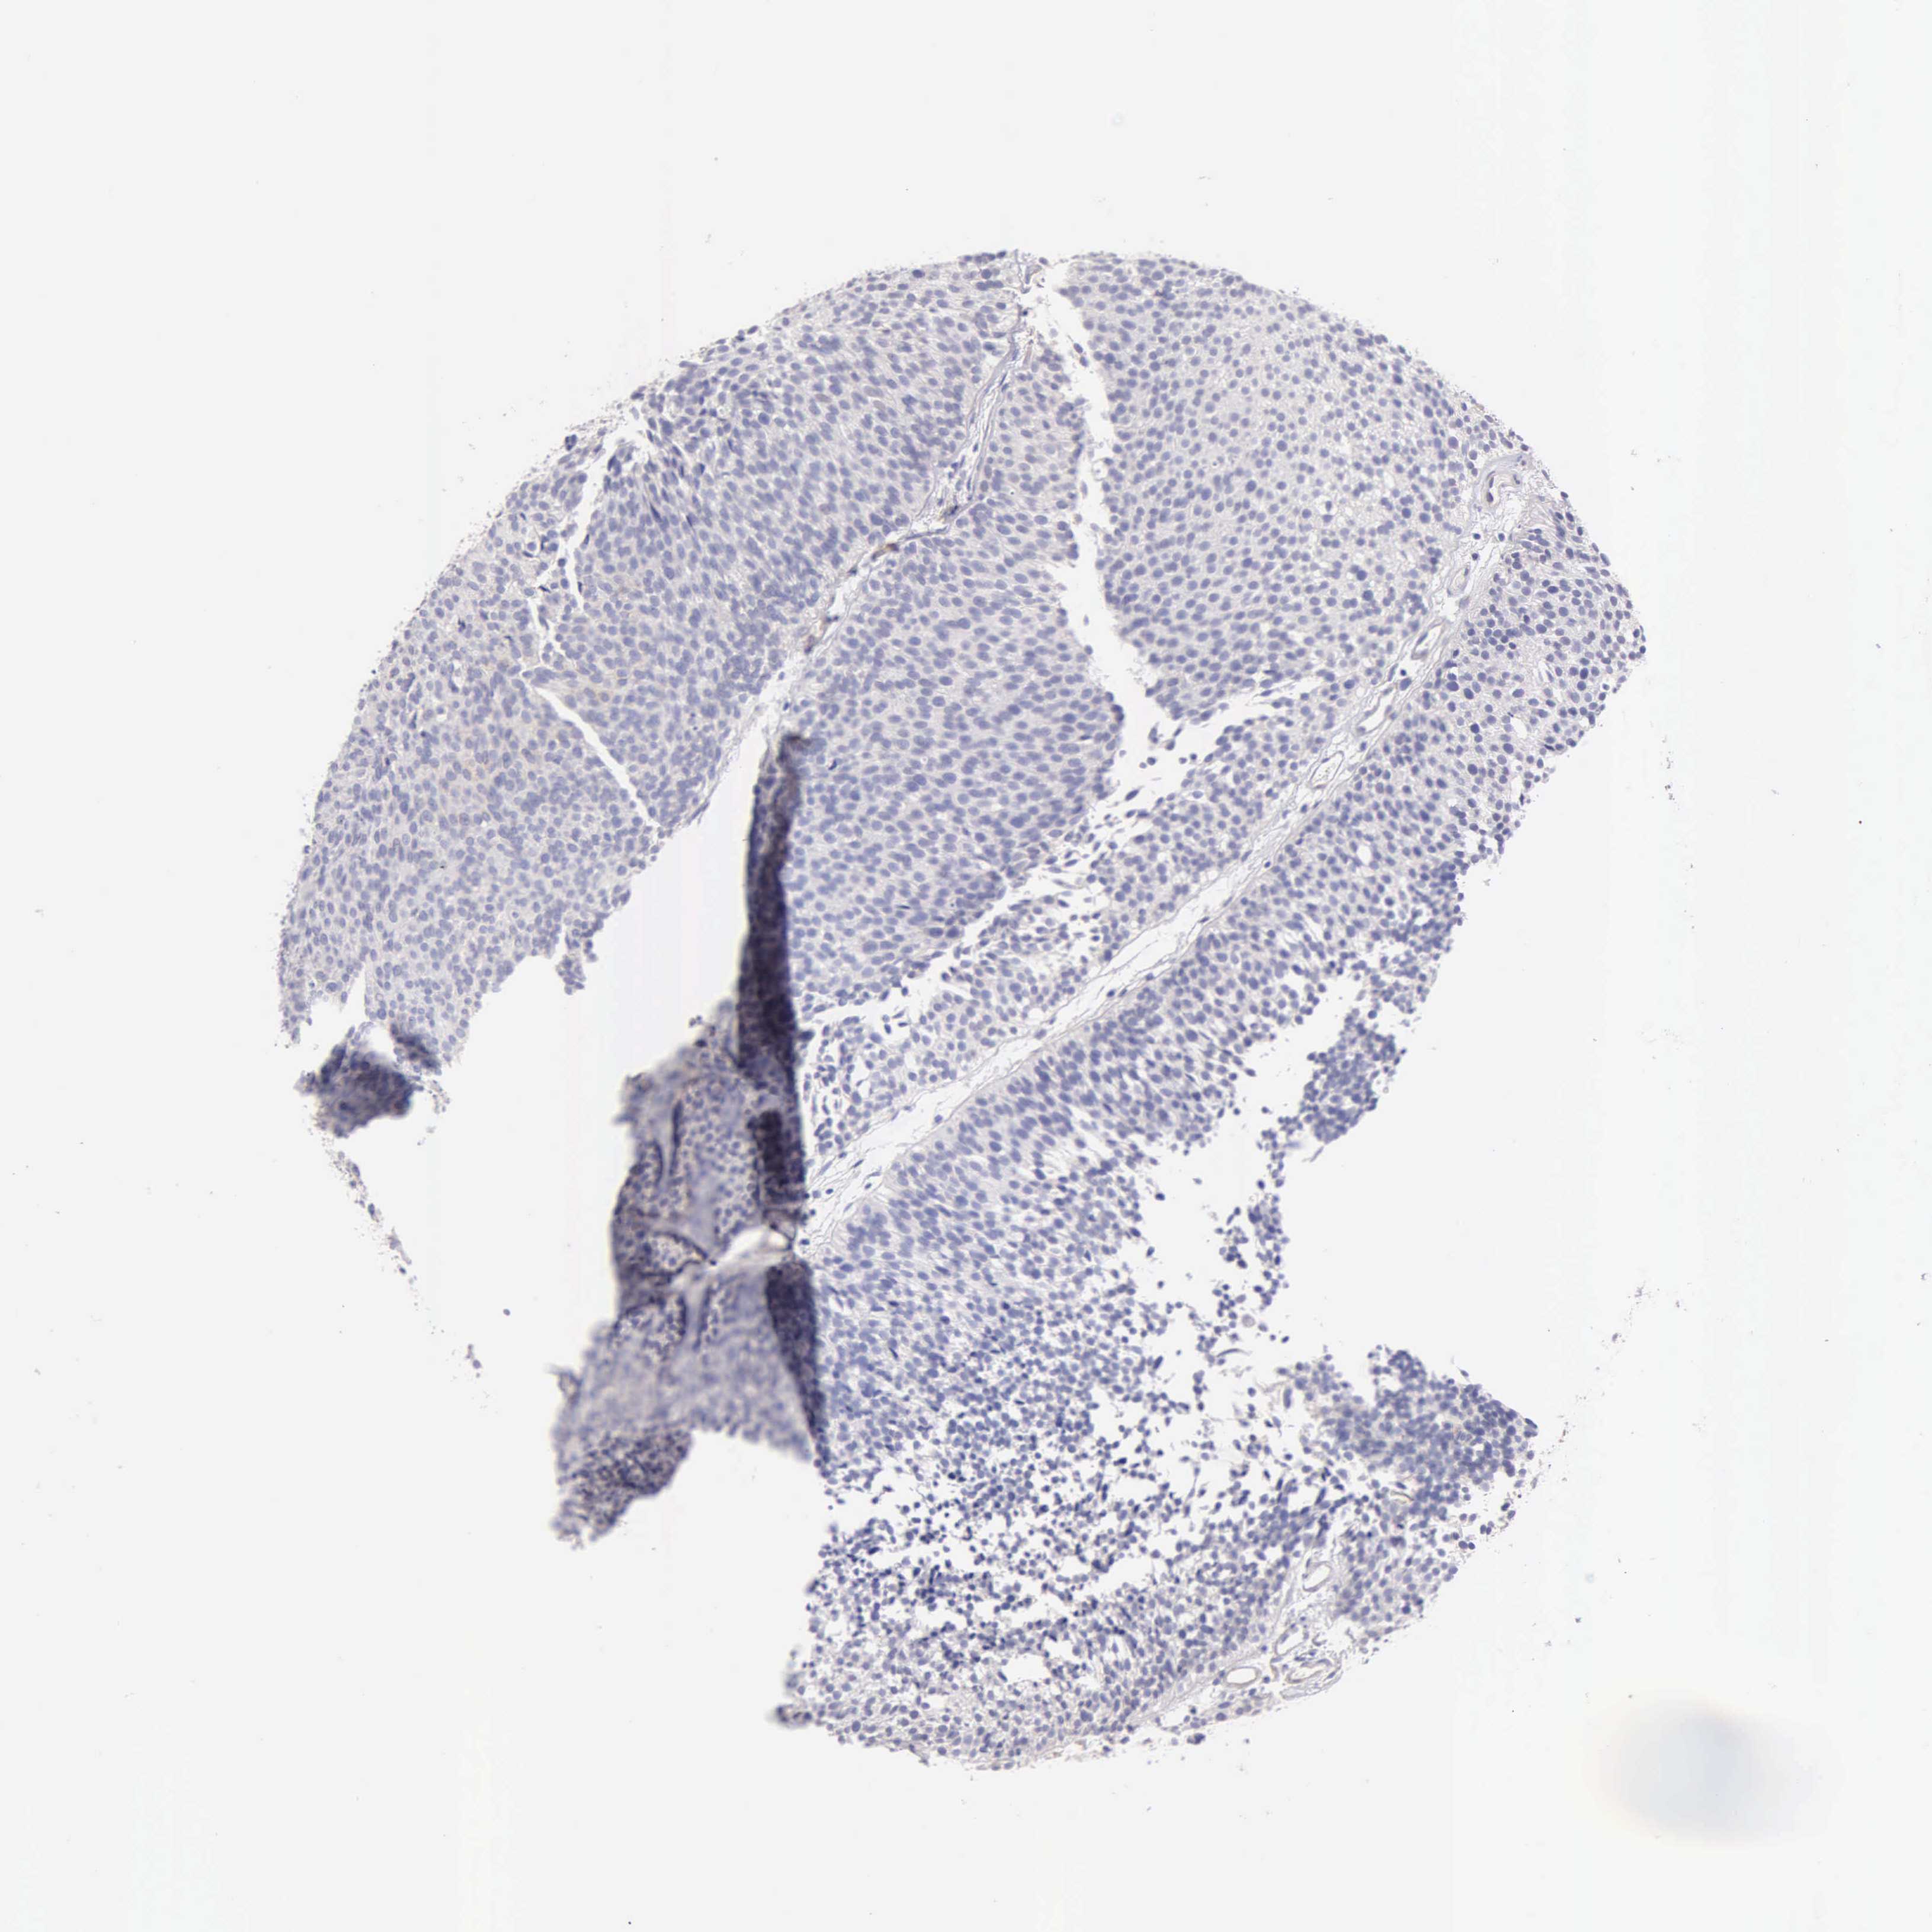

UROTHELIAL CANCER - Protein expressioni

A mouse-over function shows sample information and annotation data. Click on an image to view it in a full screen mode. Samples can be filtered based on level of antibody staining by selecting one or several of the following categories: high, medium, low and not detected. The assay and annotation is described here.

Note that samples used for immunohistochemistry by the Human Protein Atlas do not correspond to samples in the TCGA dataset.

Antibody stainingi

Antibody staining in the annotated cell types in the current human tissue is reported as not detected, low, medium, or high, based on conventional immunohistochemistry profiling in selected tissues. This score is based on the combination of the staining intensity and fraction of stained cells.

Each image is clickable and will lead to virtual microscopy that enables deeper exploration of all samples and also displays staining intensity scores, fraction scores and subcellular localization as well as patient and tissue information for each sample.

Antibody HPA001462

Antibody CAB000157

Staining

High

Medium

Low

Not detected

Intensity

Strong

Moderate

Weak

Negative

Quantity

>75%

75%-25%

<25%

None

Location

Nuclear

Cytoplasmic/membranous

Cytoplasmic/membranous,nuclear

Urothelial carcinoma, High grade